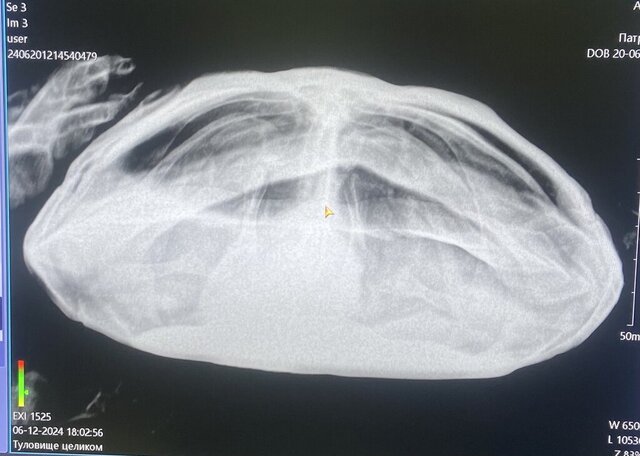

Простите, я в черновике на компьютере писала про то что испражнений нет, а в телефоне я уже редактировала и отправляла пост,  либо  удалился кусок либо не заметила. Отвезла на рентген, врач попросила посоветоваться с кем то еще из врачей кто сможет подсказать как лечить,  чтобы поставить диагноз, пока что под вопросом непроходимость кишечника, либо что-то с почкой. На снимке видно какое то вздутие. Да, аппетит есть, но еду не просит.

сможете подсказать что можно сделать исходя из снимка?

IMG_5073.jpeg

@Mavromatidi в одной проекции снимка не достаточно, нужно было делать хотя бы в двух, чтобы ещё лёгкие было видно

по этому снимку есть скопление газов в жкт. Для непроходимости черепаха должна съесть что-то инородное.

Начните делать вибротерапию - положите черепаху в контейнер без воды и поставьте на сильно вибрирующий прибор на 10-15 минут, затем сделать тёплую ванночку 32 градуса вода на 20 минут.

Да, снимки сделали 3 штуки. Скорее всего она съела кусок перчатки латексной, тк перчатка была прокусана, но следов оторванной перчатки не было. Это было 10 октября, в  20 числах ноября я заметила странное поведение. Спасибо, попробую сделать как вы сказали. Перкуссионный массжер подойдет для тряски? Сколько раз делать такую процедуру?

@Mavromatidi

на этих снимках я не вижу проблем